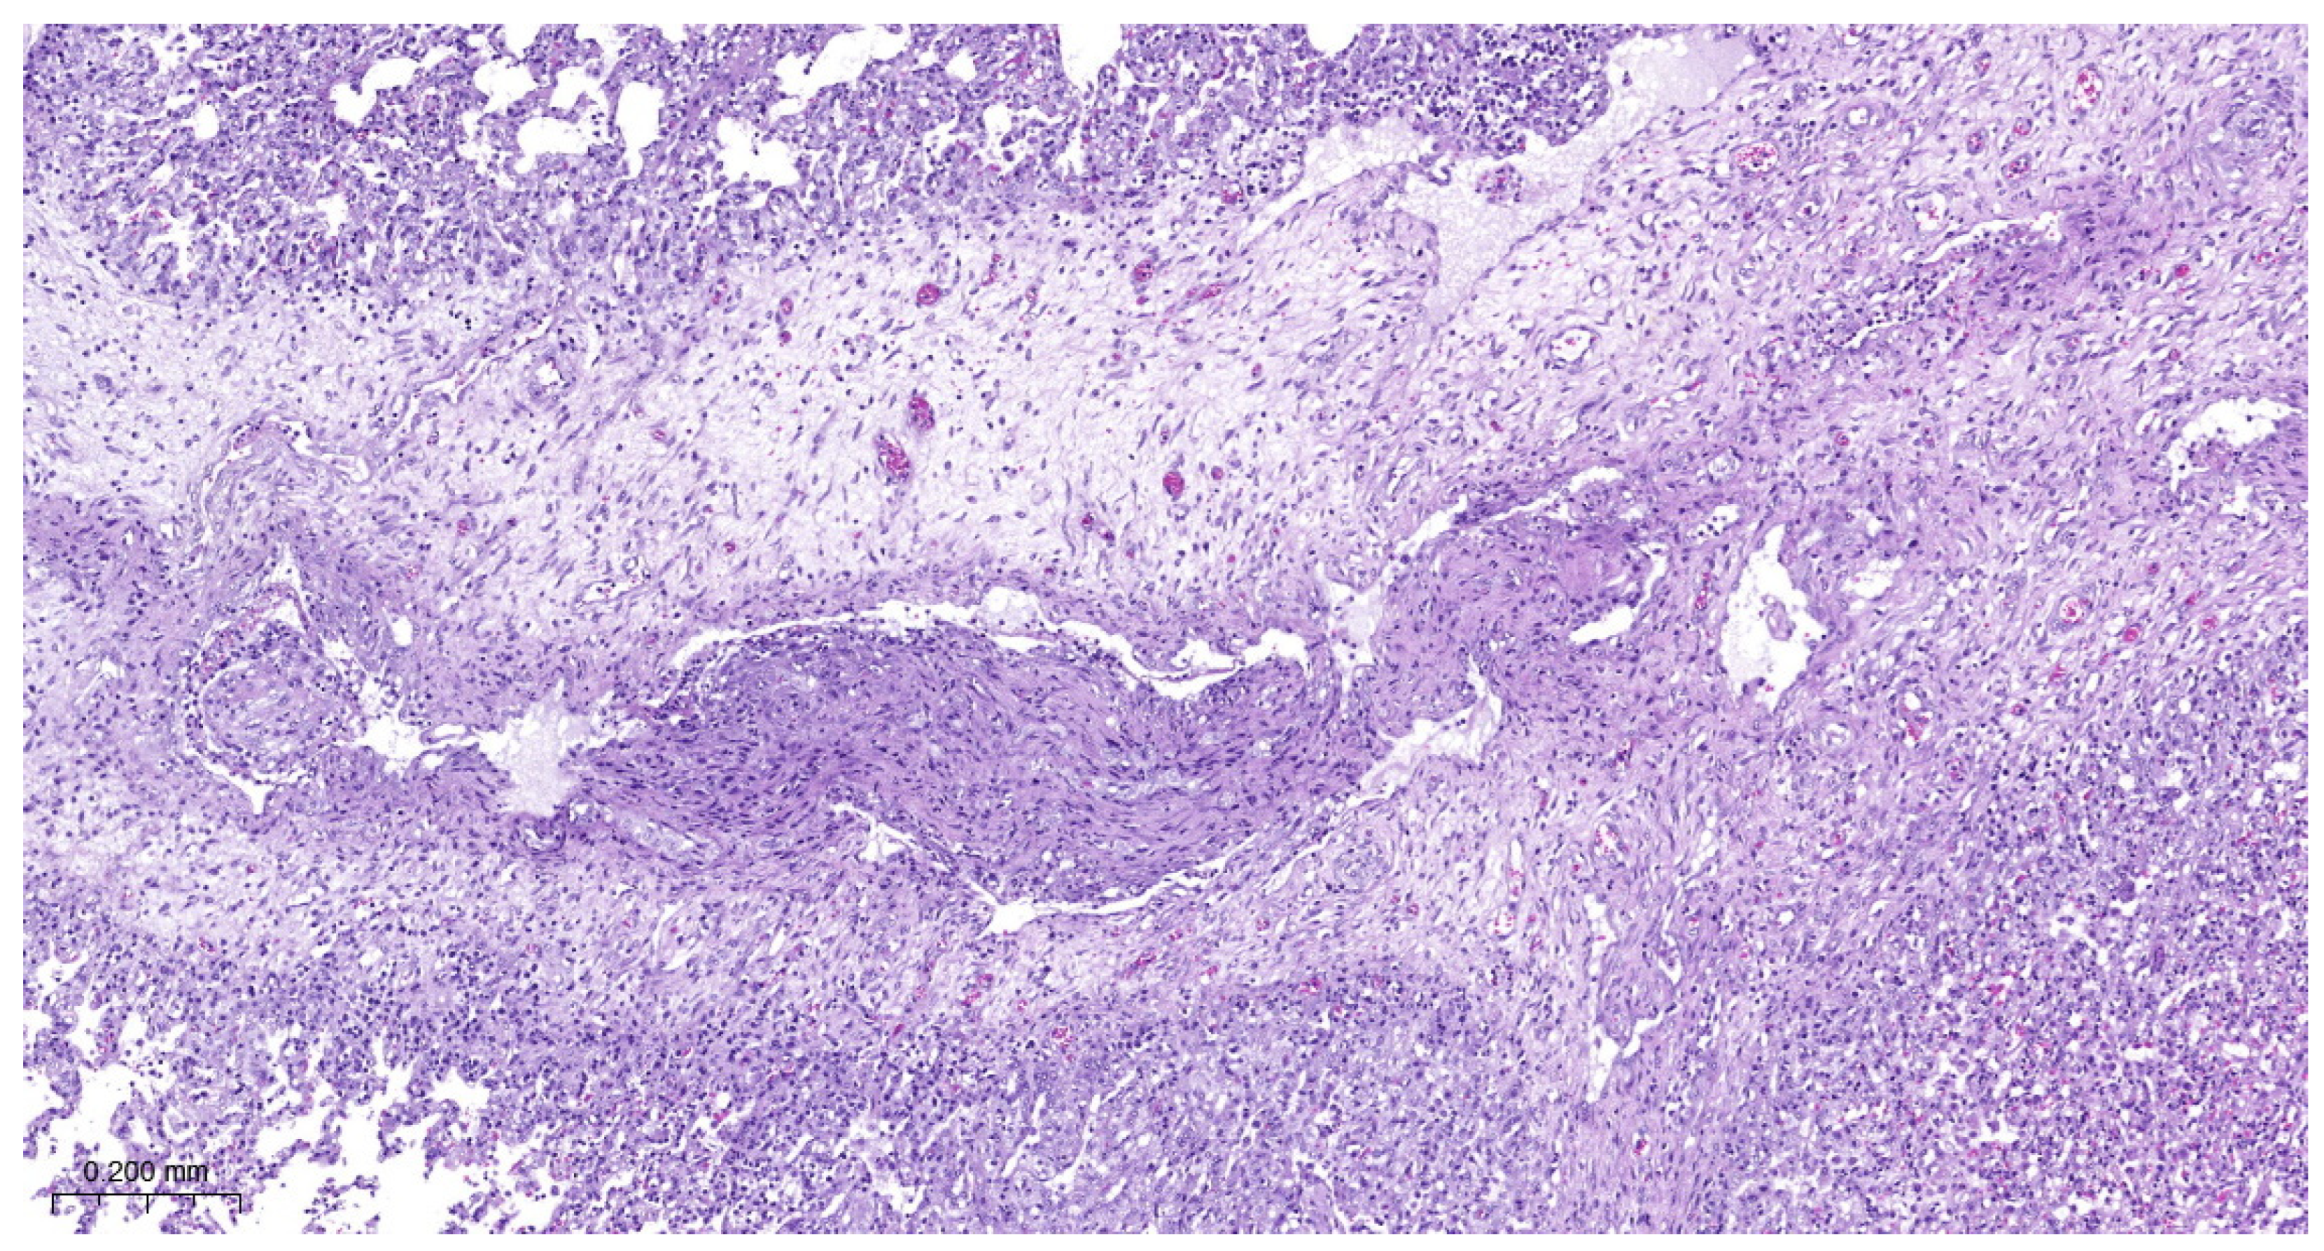

3.4. Histopathology